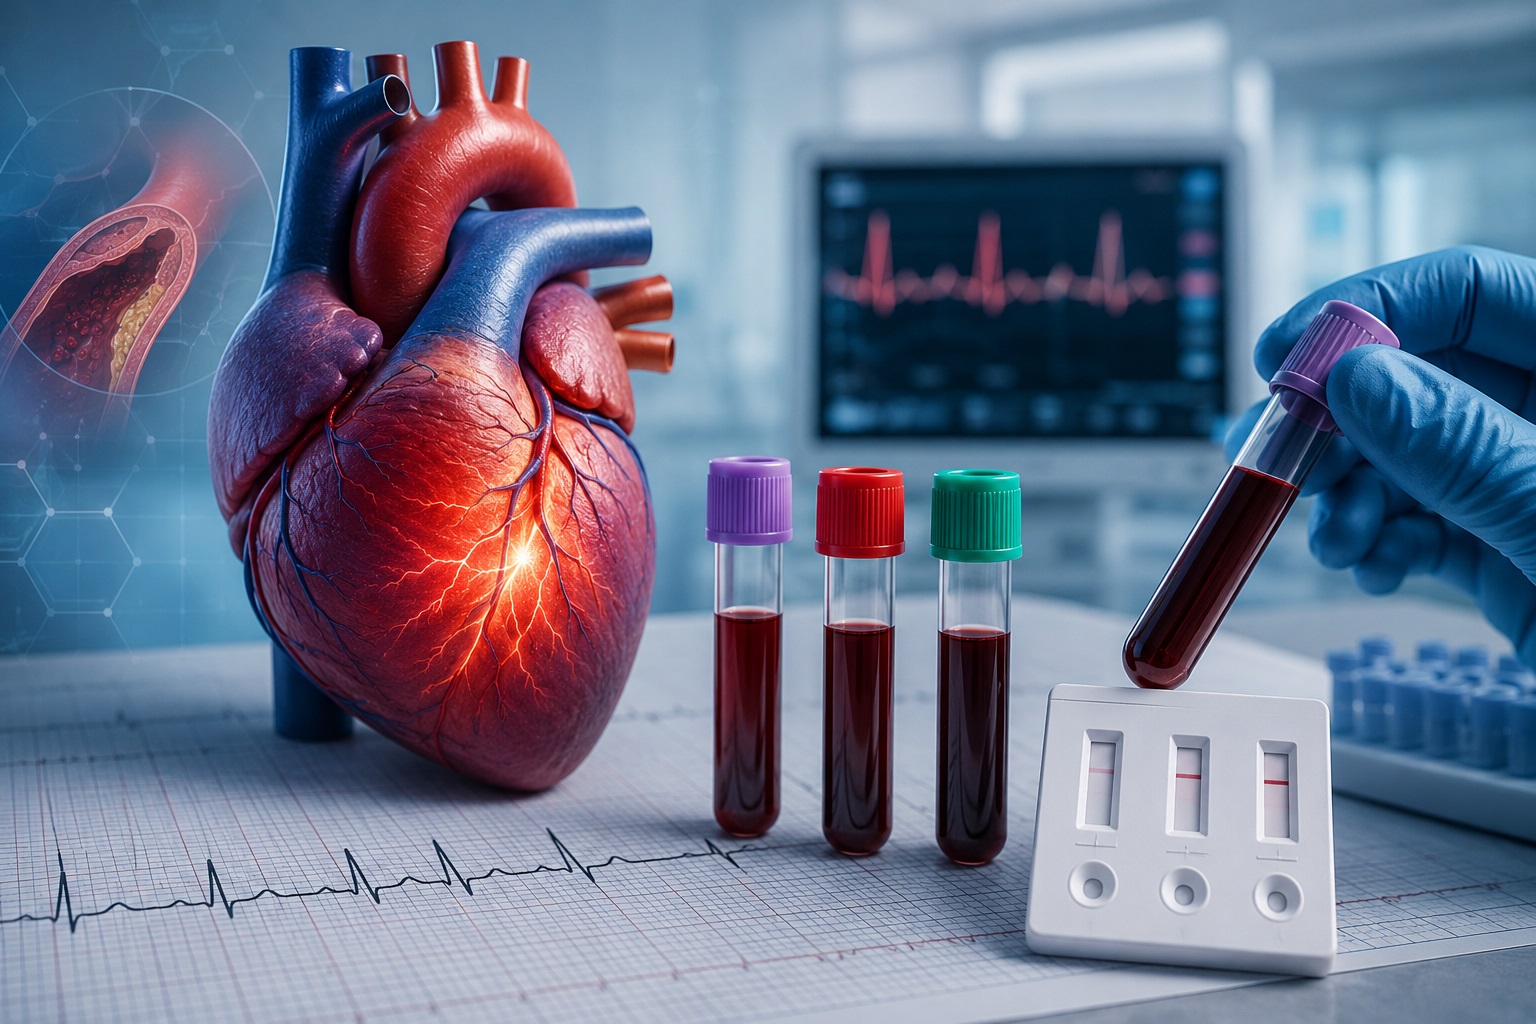

Primele ore pot schimba prognosticul unui pacient. Rolul biomarkerilor cardiaci în diagnosticul rapid al infarctului miocardic

Bolile cardiovasculare continuă să reprezinte principala cauză de deces în România și în întreaga Europă. Potrivit Profilului de sănătate al României, publicat de Comisia Europeană și OECD, boala cardiacă ischemică și accidentul vascular cerebral rămân printre principalele cauze de mortalitate evitabilă și tratabilă din țara noastră. În plus, România înregistrează una dintre cele mai ridicate rate de mortalitate cardiovasculară din Uniunea Europeană, ceea ce evidențiază importanța diagnosticului precoce și a intervenției terapeutice rapide.

În cazul infarctului miocardic acut, timpul reprezintă unul dintre cei mai importanți factori care influențează prognosticul pacientului. Fiecare minut de întârziere până la restabilirea fluxului sanguin către miocard înseamnă pierderea ireversibilă a unui număr tot mai mare de cardiomiocite. Acest principiu, sintetizat în literatura de specialitate prin expresia „time is muscle”, stă la baza tuturor algoritmilor moderni de diagnostic și tratament ai sindroamelor coronariene acute.

În acest context, biomarkerii cardiaci au devenit o componentă indispensabilă a medicinei de urgență, completând informațiile furnizate de examenul clinic și electrocardiogramă și contribuind la stabilirea rapidă a diagnosticului.

De ce electrocardiograma nu este întotdeauna suficientă?

Electrocardiograma (ECG) reprezintă prima investigație efectuată la pacientul care se prezintă cu durere toracică. Totuși, modificările electrocardiografice nu sunt întotdeauna evidente în primele ore de la debutul infarctului miocardic. Există situații în care traseul ECG poate fi nespecific sau chiar aparent normal, în ciuda existenței unei leziuni miocardice în evoluție.

În plus, simptomele pot fi atipice, în special la femei, pacienți vârstnici sau persoane cu diabet zaharat, unde durerea toracică clasică poate lipsi sau poate fi înlocuită de dispnee, fatigabilitate sau disconfort epigastric.

Din acest motiv, ghidurile internaționale recomandă întotdeauna interpretarea electrocardiogramei împreună cu biomarkerii cardiaci și tabloul clinic al pacientului.

Biomarkerii cardiaci nu apar simultan în circulație

Un aspect esențial în interpretarea analizelor de laborator este faptul că biomarkerii cardiaci nu sunt eliberați simultan după producerea unei leziuni miocardice.

Fiecare marker are o cinetică proprie, caracterizată printr-un moment diferit de apariție în sânge, un vârf de concentrație și o perioadă specifică de persistență în circulație. Această dinamică reflectă mecanismele biologice prin care cardiomiocitele lezate eliberează diferitele proteine intracelulare și explică de ce alegerea biomarkerului potrivit depinde și de momentul prezentării pacientului la unitatea de primiri urgențe.

Tocmai această complementaritate stă la baza utilizării panelurilor multimarker în diagnosticul infarctului miocardic acut.

Mioglobina, CK-MB și troponina cardiacă I, cei trei biomarkeri cu trei roluri complementare

Mioglobina, primul biomarker detectabil

Mioglobina este una dintre primele proteine eliberate în circulație după producerea unei leziuni miocardice, devenind detectabilă în aproximativ 2-4 ore de la debutul injuriei. Datorită acestei cinetici rapide, a fost utilizată timp de mulți ani ca marker precoce al infarctului miocardic.

Totuși, specificitatea sa este limitată, deoarece este prezentă atât în mușchiul cardiac, cât și în musculatura scheletică. Astfel, concentrații crescute pot apărea și în traumatisme musculare, rabdomioliză, convulsii sau după efort fizic intens.

CK-MB, biomarkerul care a schimbat diagnosticul infarctului

Creatin Kinaza-MB (CK-MB) a reprezentat, timp de decenii, biomarkerul standard utilizat pentru diagnosticul infarctului miocardic acut.

Concentrațiile sale cresc, în general, la 3-8 ore după debutul leziunii, ating un maxim în aproximativ 9-30 de ore și revin la valorile bazale în 48-72 de ore. Comparativ cu mioglobina, CK-MB oferă o specificitate mai ridicată pentru afectarea miocardică și poate furniza informații utile privind dinamica leziunii.

Troponina cardiacă I, biomarkerul de referință

În prezent, troponina cardiacă I (cTnI) reprezintă biomarkerul de referință recomandat de ghidurile internaționale pentru diagnosticul infarctului miocardic acut.

Specificitatea sa ridicată pentru țesutul miocardic și persistența în circulație timp de 6-10 zile permit identificarea leziunilor miocardice chiar și la pacienții care se prezintă tardiv la evaluare. Totodată, valorile troponinei sunt mult mai puțin influențate de leziunile musculaturii scheletice comparativ cu ceilalți biomarkeri.

De ce sunt utilizați împreună?

În medicina de laborator modernă nu mai vorbim despre un biomarker „perfect”, ci despre interpretarea integrată a biomarkerilor în funcție de momentul prezentării pacientului și de contextul clinic.

Mioglobina oferă informații în faza foarte precoce a leziunii, CK-MB completează evaluarea dinamicii acesteia, iar troponina cardiacă I confirmă cu cea mai mare specificitate existența unei leziuni miocardice.

Interpretarea acestor markeri împreună cu electrocardiograma și tabloul clinic permite o caracterizare mult mai precisă a pacientului și susține deciziile terapeutice în primele ore, atunci când timpul influențează direct prognosticul.

O soluție integrată pentru evaluarea rapidă a biomarkerilor cardiaci

Pornind de la această complementaritate biologică, DDS Diagnostic a lansat Testul Rapid Combo Mioglobină / CK-MB / Troponină cardiacă I, destinat utilizării profesionale în laboratoare de analize medicale, unități de primiri urgențe și alte servicii medicale care necesită o evaluare rapidă a pacienților cu suspiciune de infarct miocardic acut.

Testul utilizează o metodă imunocromatografică pentru detectarea calitativă a celor trei biomarkeri din sânge integral, ser sau plasmă, oferind informații complementare despre diferitele etape ale leziunii miocardice într-o singură determinare.

Prin integrarea mioglobinei, CK-MB și troponinei cardiace I într-un singur test, clinicianul beneficiază de o imagine biologică mai completă asupra procesului de lezare miocardică, informațiile obținute putând susține evaluarea rapidă a pacientului în asociere cu examenul clinic, electrocardiograma și celelalte investigații recomandate de ghidurile de practică medicală.

Diagnosticul rapid începe cu informația potrivită

Evoluția medicinei de laborator din ultimele decenii a demonstrat că succesul diagnosticului nu depinde exclusiv de rapiditatea obținerii rezultatului, ci și de alegerea biomarkerilor potriviți și de interpretarea lor în contextul clinic adecvat.

În infarctul miocardic acut, fiecare oră poate influența prognosticul pacientului. Din acest motiv, utilizarea unor metode moderne de testare, capabile să integreze biomarkeri cu profile biologice complementare, reprezintă un pas important în optimizarea procesului de diagnostic și în susținerea deciziilor clinice bazate pe dovezi.